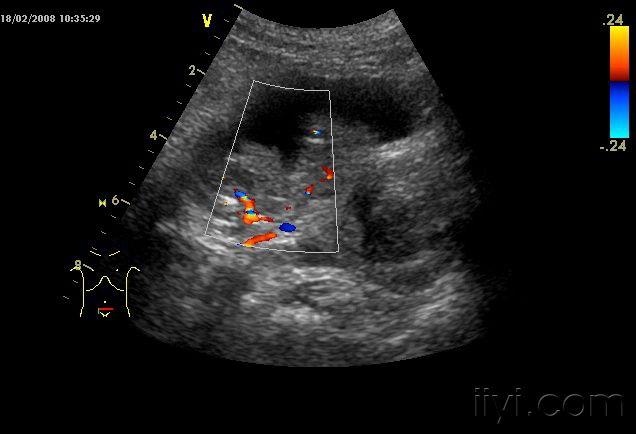

另一处

肿瘤内血供